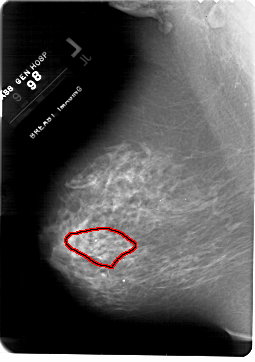

FILE: A_1817_1.LEFT_MLO.OVERLAY

TOTAL_ABNORMALITIES 1

ABNORMALITY 1

LESION_TYPE CALCIFICATION TYPE PLEOMORPHIC DISTRIBUTION SEGMENTAL

ASSESSMENT 4

SUBTLETY 4

PATHOLOGY MALIGNANT

TOTAL_OUTLINES 1

BOUNDARY